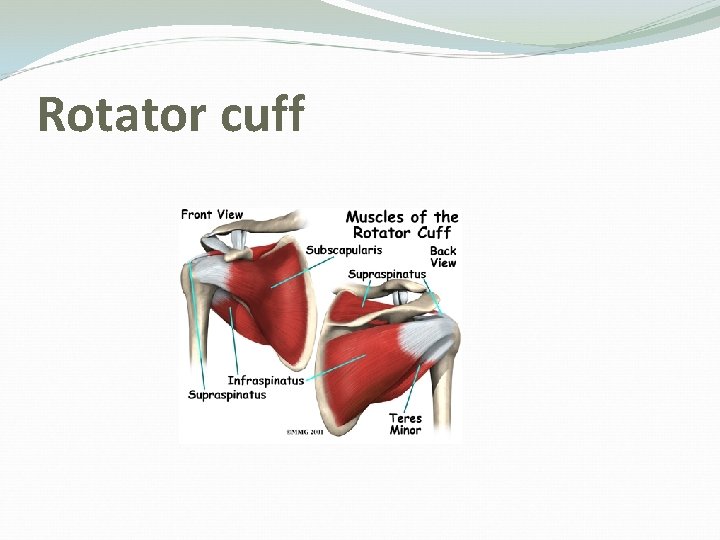

Shoulder Anatomy: Rotator Cuff Muscles Depress humeral head against glenoid

Shoulder anatomy: Rotator cuff muscles Supraspinatus: Abduction Infraspinatus: External rotation Teres Minor: External rotation Subscapularis: Internal rotation

Rotator cuff

Rotator cuff muscles Supraspinatus: Initiation of abduction + external rotation Infraspinatus: External rotation Subscapularis: Internal rotation Teres Minor: Internal rotation

Cont” Function of rotator cuff muscles Keep the humeral head centered on the glenoid regardless of the arm’s position in space. Generally work to depress the humeral head while powerful deltoid contracts